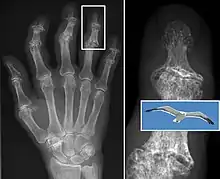

Diagnosis is made with reasonable certainty based on history and clinical examination.[51][52] X-rays may confirm the diagnosis. The typical changes seen on X-ray include: joint space narrowing, subchondral sclerosis (increased bone formation around the joint), subchondral cyst formation, and osteophytes.[53] Plain films may not correlate with the findings on physical examination or with the degree of pain.[54]

Primary osteoarthritis of the left knee. Note the osteophytes, narrowing of the joint space (arrow), and increased subchondral bone density (arrow).